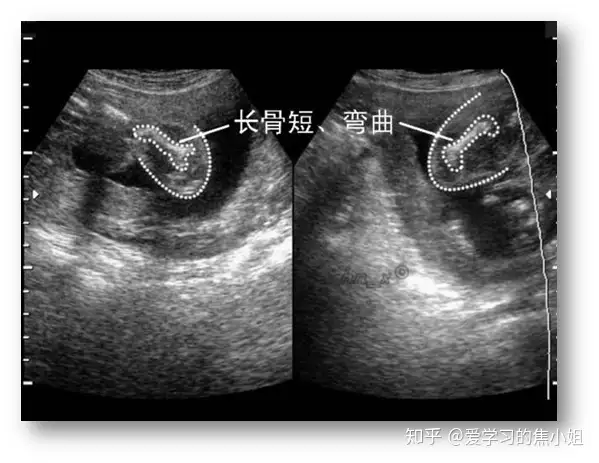

十一、胎儿肱骨/股骨短小

胎儿肱骨/股骨短小:小于标准曲线的第2.5百分位,或小于以双顶径为标准计算孕龄的第10百分位以下。

长骨明显缩短或外表异常,可能是骨骼发育不全,短长骨是胎儿宫内生长迟缓的早期警报,肱骨或股骨缩短均与染色体异常的风险增加有关,肱骨在辨识21三体方面更可靠。